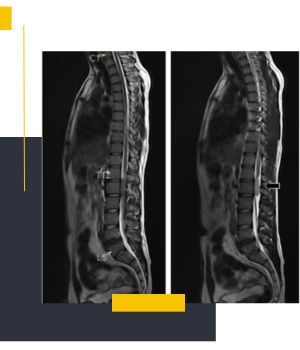

تصویربرداری توتال اسپاین (Full Spine Imaging) روشی تخصصی در حوزه تصویربرداری پزشکی است که برای مشاهده تمام طول ستون فقرات از ناحیه گردنی (Cervical) تا دنبالچه (Sacral) به کار می‌رود. برخلاف رادیوگرافی‌های معمول که صرفاً بخش محدودی از مهره‌ها مانند گردن، سینه یا کمر را در هر نوبت نشان می‌دهند تصویربرداری کامل ستون فقرات به ‌یاری فناوری دیجیتال و تکنیک Stitching نمایی کامل و یکپارچه از همه مهره‌ها ارائه می‌دهد.

در این روش معمولاً چندین تصویر متوالی از بخش‌های مختلف ستون مهره‌ها تهیه و سپس به هم متصل می‌شود تا تصویر نهایی بدون خط یا شکست و با نمایش کامل انحرافات یا تغییرات ساختاری به دست آید.

یکی از نقاط تمایز کلیدی این روش بهره‌مندی از فناوری Stitching یا Total Spine است. در این روش دستگاه تصویربرداری دیجیتال چندین تصویر متوالی از بخش‌های مختلف ستون فقرات می‌گیرد و سپس با استفاده از نرم‌افزار پیشرفته تصاویر به‌ شکل کاملاً دقیق و یکپارچه به هم متصل می‌شوند. نتیجه تصویری پیوسته و بدون خط شکست است که تمامی جزئیات مهره‌ها، دیسک‌ها و مفاصل را با کیفیت مطلوب نشان می‌دهد. این فناوری به‌ ویژه در مشاهده انحرافات (مثل اسکولیوز)، بررسی زاویه کب و پایش اثرات درمانی اهمیت بسیار زیادی دارد.

مقایسه وضعیت قبل و بعد درمان: تحلیل تصاویر تهیه‌ شده در بازه‌های زمانی مختلف، میزان اثربخشی مداخلات درمانی و تغییرات ساختاری را به پزشک نشان می‌دهد.

امکان پیگیری درمان و مقایسه تصاویر در بازه‌های مختلف: ویژگی ترکیب تصاویر در این روش مقایسه پیش از درمان، حین درمان و پس از درمان را ساده می‌سازد. پزشکان می‌توانند روند بهبود یا تغییرات ساختاری را با جزئیات بررسی کنند.